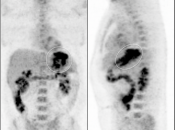

Recurrence & Restaging

• Restaging suspected recurrence.

• Distinguishing recurrence from post-therapeutic inflammation.